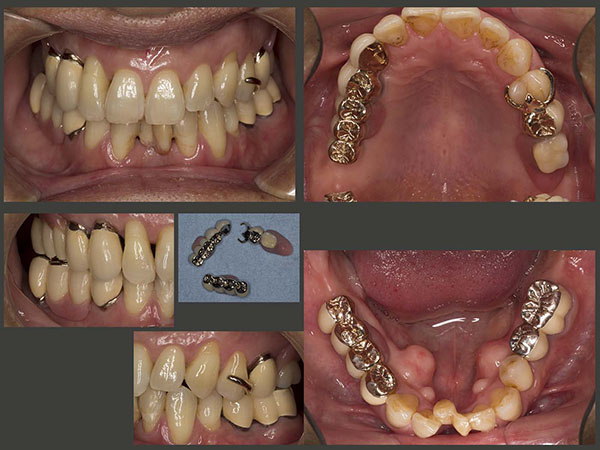

3.重度歯周病にコーヌス義歯で対応(1)

2012年2月初診,52歳男性.右下1および右上3の歯がグラグラするが主訴.歯周病がかなり進行しており,保存不可能な歯があるが,本人はどうしても歯を抜きたくないとのこと.まず,歯周基本治療を行い,右上3を抜髄し,自然挺出を開始した.

当院の環境に慣れてきたところで,保存不可能な歯の抜歯を行った.スライドにみられるように,歯石が根尖まで付着している.このような歯を放置すると,顎堤が吸収し,義歯の安定が得られなくなってしまう.

なお,抜歯を行うにあたって,2012年11月,即時義歯を装着した.上顎の口蓋を覆う義歯を装着したため,患者さんは違和感を強く訴えた.その後自然挺出を行った右上3および左下5に,歯周外科処置を施した.

2014年9月,初診終了時の状態.片側処理の可撤式義歯を合計3個装着した.支台歯の歯周ポケットは3mm以下に改善したが,予後が心配な歯であることに変わりはない.そこで,清掃性が良く,将来の変化に対応しやすいコーヌス義歯を採用することにした.左下も可撤式にしたかったが,経済的な負担も大きくなるので,左下5,6は,クラウンで連結固定した.下顎前歯は,ここで咬まないということを条件に,抜去した歯を単に接着剤(スーパーボンド)で隣在歯と固定した.また,みるからに咬合力が強いと思われることから,意識して咬み過ぎないように,さらに日中の咬みしめ(TCH)に特に注意するよう指導した.

コーヌス義歯装着時.片側遊離端欠損症例には通常2本の支台歯が必要となる.(中・側切歯は含めず.)したがって,左上にも2本の支台歯が必要となる.今回は左上4がバージントゥースであることから,審美的には良くないが,歯を削去しないですむクラスプを用いた.なお,欠損部から2本目の支台歯の目的は,1本目の支台歯に加わる側方力を減らすことであると私は考えている.

初診時および初診終了時のパノラマX線写真の比較.保存不可能な歯の抜去を4本,ヘミセクションを2本行った.自然挺出を行った右上3および左下5の歯周ポケットが改善したことから,本来人間の持つ自然治癒力の高さに驚かされた.